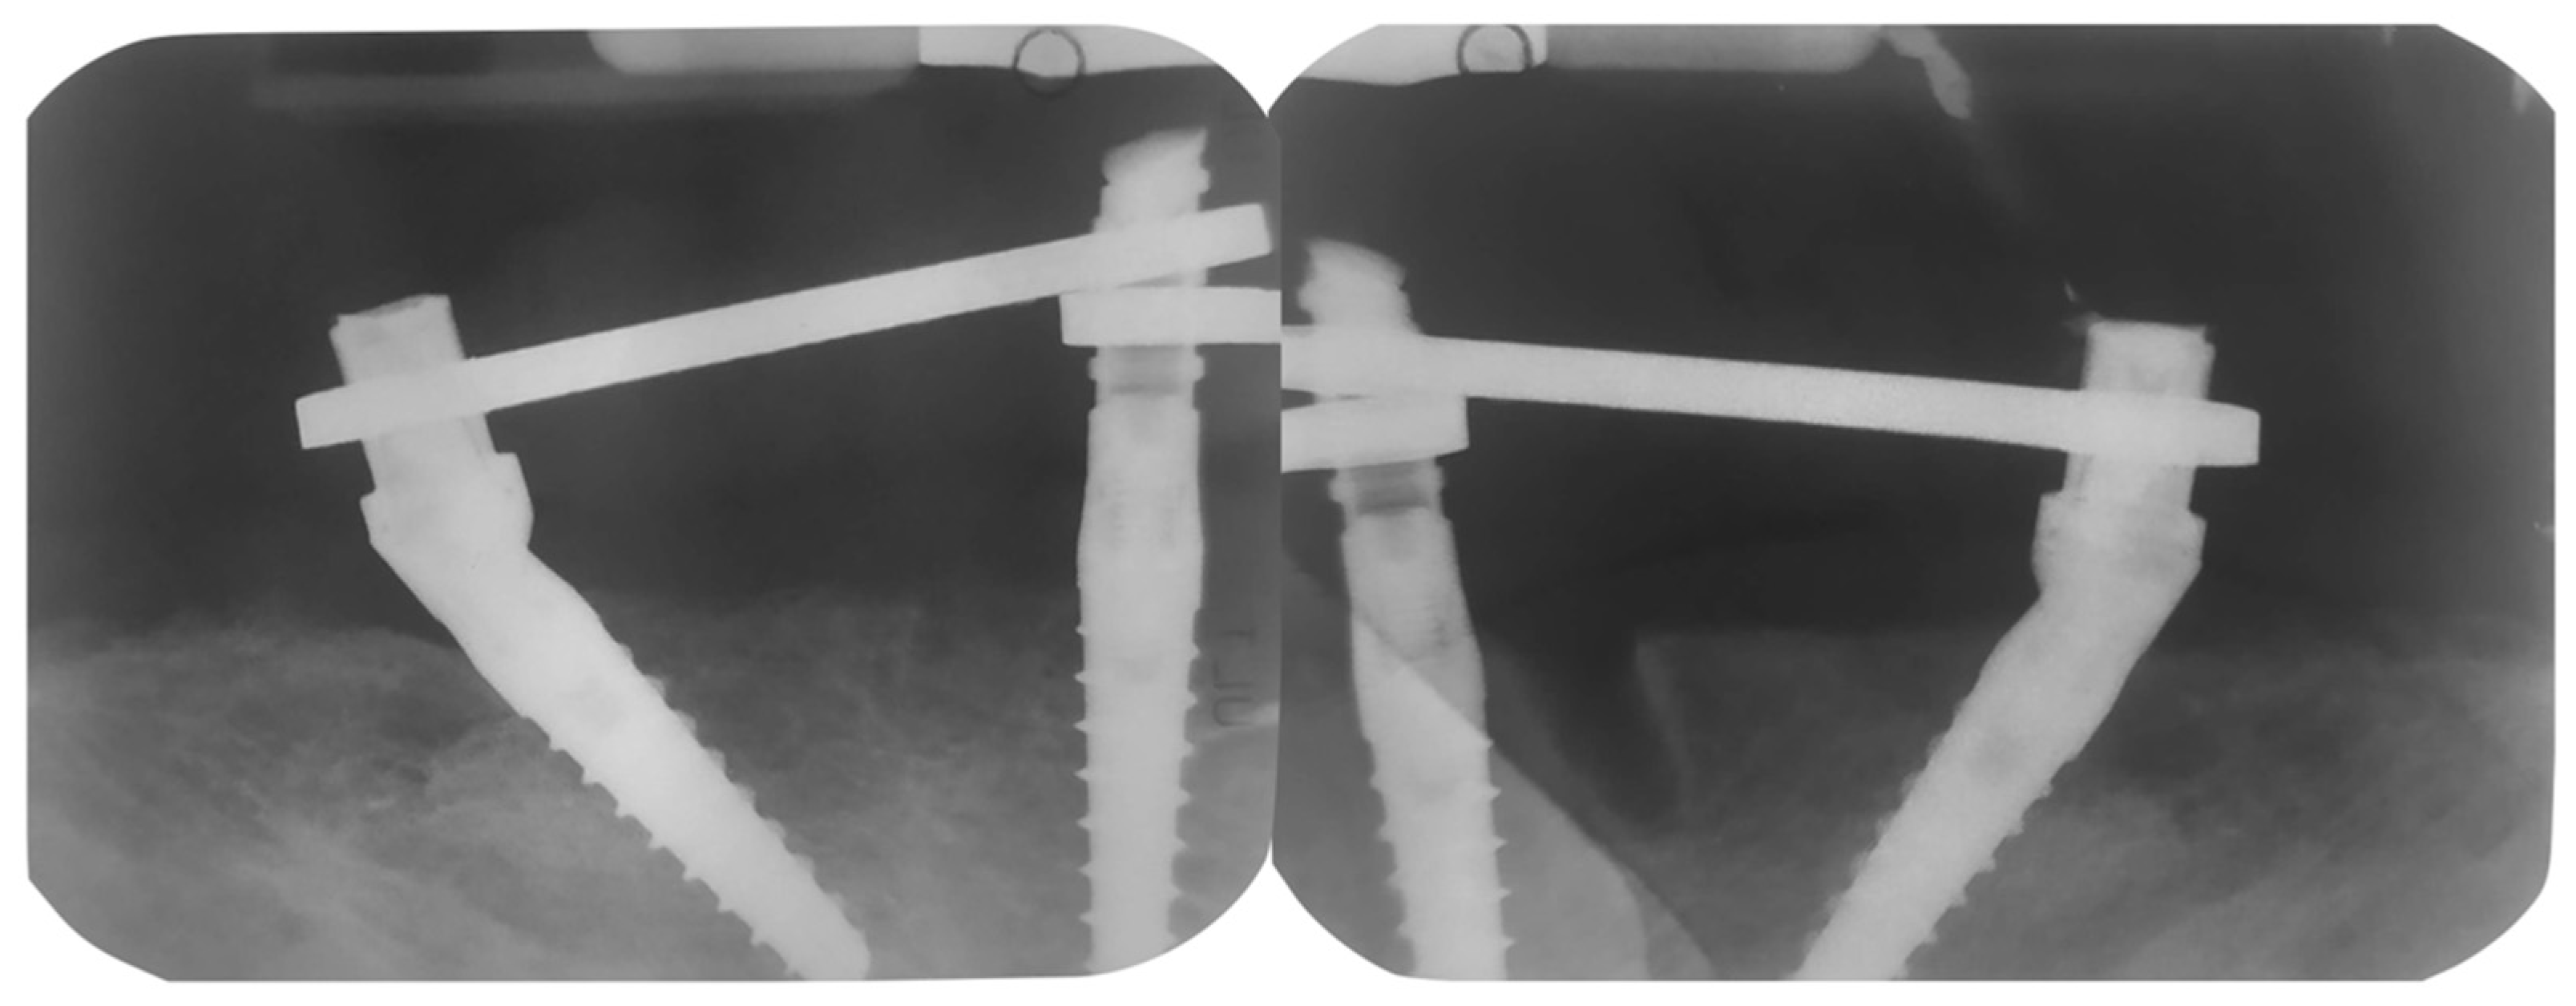

2. Case Report

Surgery Appointment

3. Results